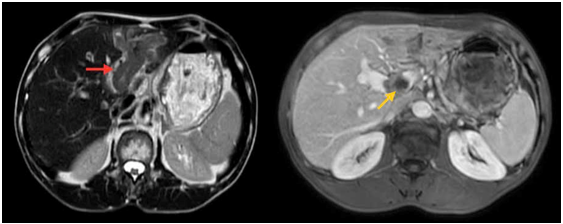

Case lâm sàng: Điều trị miễn dịch kết hợp thuốc kháng tăng sinh mạch cho bệnh nhân ung thư biểu mô tế bào gan tại trung tâm y học hạt nhân và ung bướu – BV Bạch Mai

Case lâm sàng: Điều trị miễn dịch kết hợp thuốc kháng tăng sinh mạch cho bệnh nhân ung thư biểu...